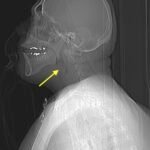

Epiglottitis is historically known to be a disease of childhood. However, since the implementation of the Haemophilus influenzae type B vaccination, there has been an increasing incidence within the adult population. This is a case report of a 36-year-old male who presented to the emergency department (ED) in severe respiratory distress with complaints of a sore throat, shortness of breath, odynophagia, dysphagia, and hoarseness. Physical exam revealed biphasic stridor, tachycardia, tachypnea, and an erythematous uvula. Imaging of his neck revealed findings consistent with epiglottitis containing nonspecific air. The patient was rapidly intubated, started on broad spectrum antibiotics and dexamethasone. He was admitted for intensive medical management with Otolaryngology consultation. This case report highlights the importance of rapid recognition and diagnosis of epiglottitis in an adult population to prevent morbidity and mortality.